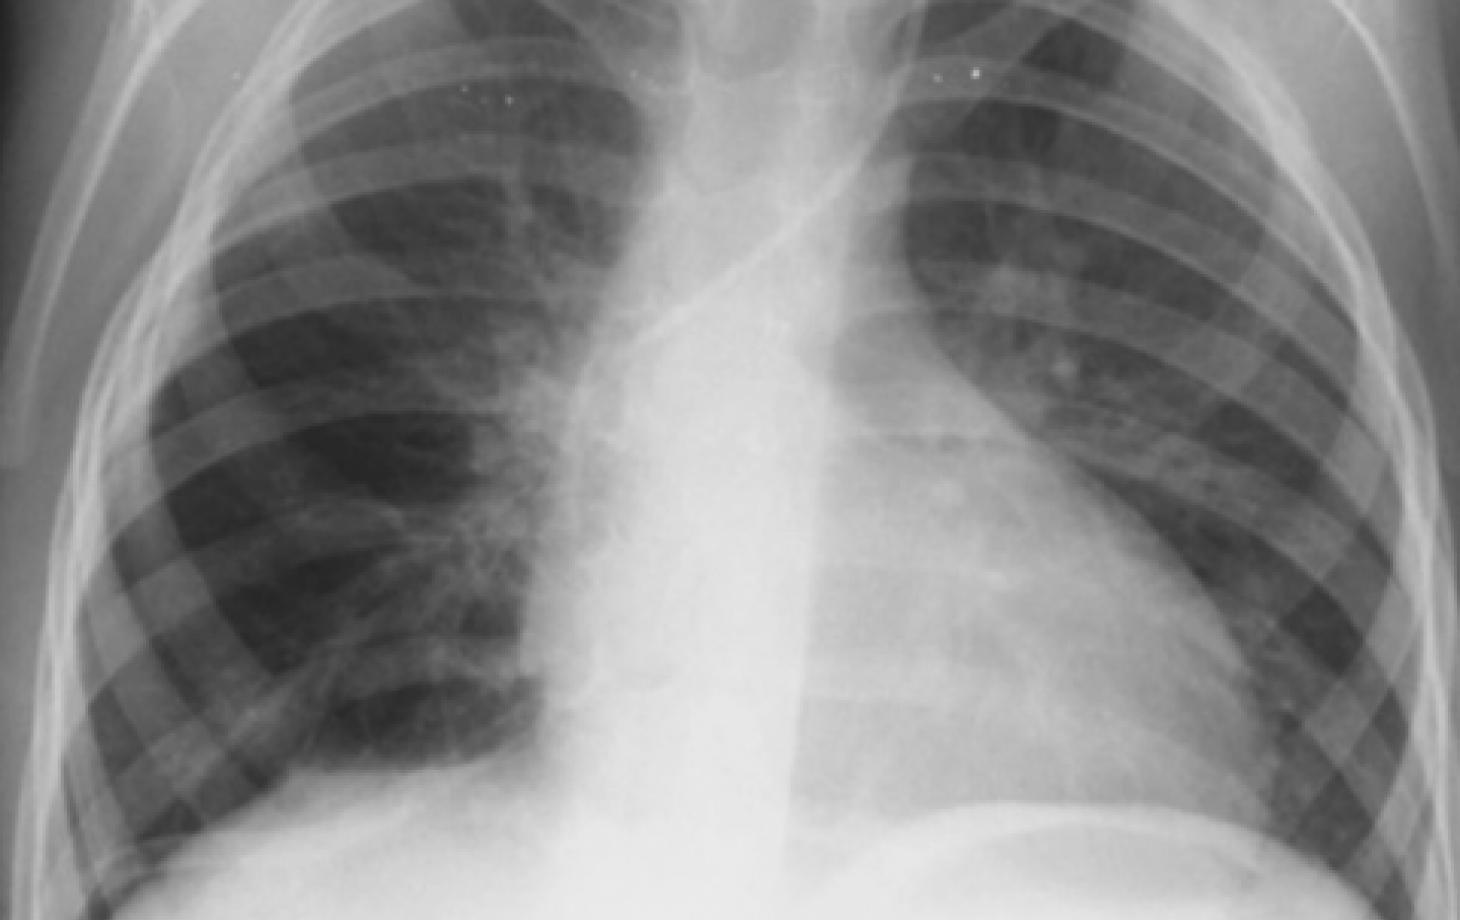

Опухоль размером примерно 12 × 9 × 10 сантиметров занимала около 80% области грудной клетки. Фото Центра детской хирургии им. Н. Георгиу